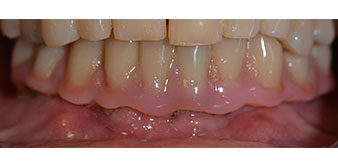

The 64-year-old patient presented with residual dentition of teeth 38, 33 and 43 and a clasp denture in the mandible (Fig. 1 and 2).

residual dentition

Fig. 2